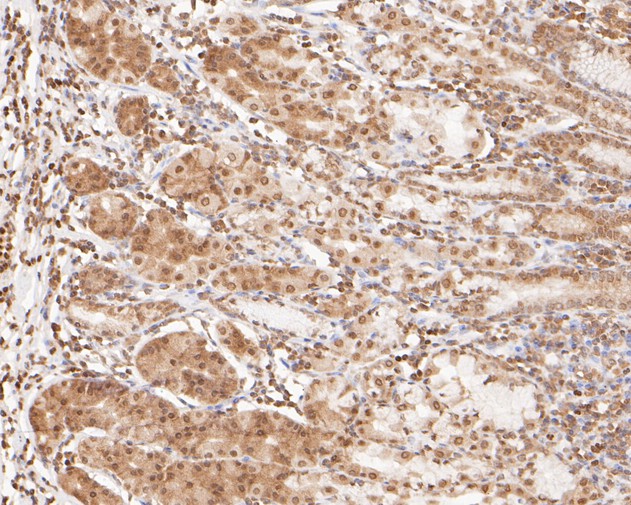

Immunohistochemical analysis of paraffin-embedded human colon carcinoma tissue using anti-OC-3 antibody. The section was pre-treated using heat mediated antigen retrieval with sodium citrate buffer (pH 6.0) (high pressure) for 2 minutes. The tissues were blocked in 5% BSA for 30 minutes at room temperature, washed with ddH2O and PBS, and then probed with the primary antibody (HA500470, 1/400) for 30 minutes at room temperature. The detection was performed using an HRP conjugated compact polymer system. DAB was used as the chromogen. Tissues were counterstained with hematoxylin and mounted with DPX.